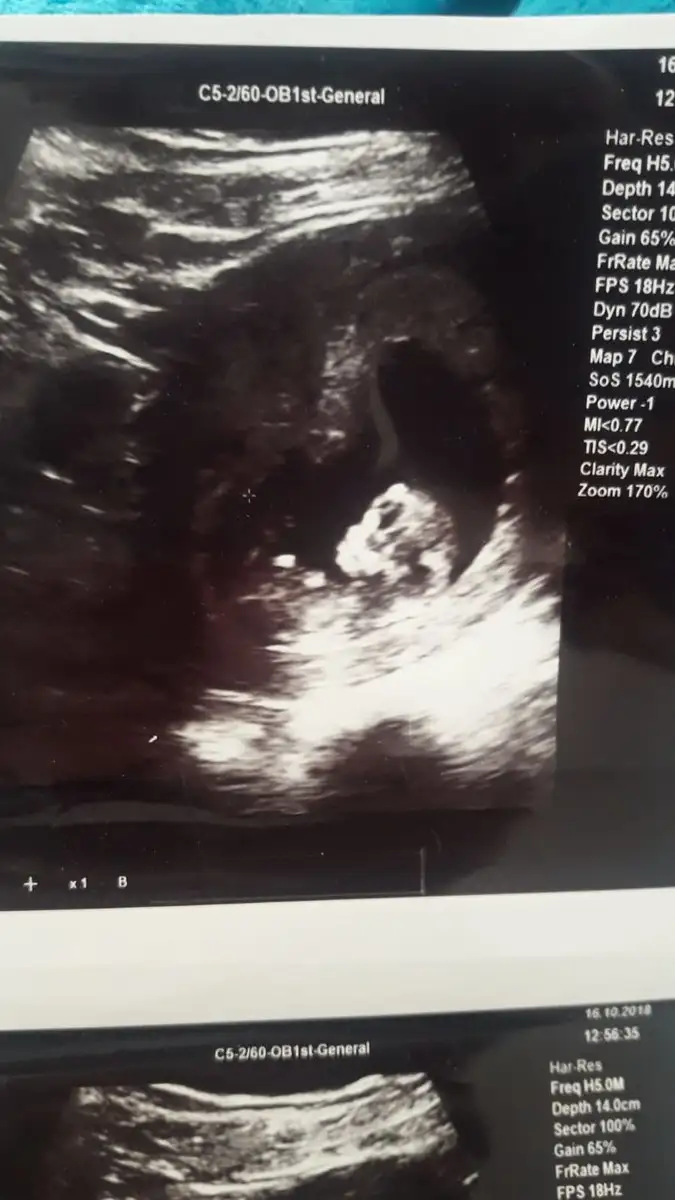

• bebişim 2.webp

bebişim 2.webp

33,2 KB · Görüntüleme: 127

Ya minik şey seni kafasina bak ♥️

Maşallah nasılda güzel annesi..

Erkek gibi hissettim benzettim ben. Sağlıcakla gelsin ♥️

Dr da erkege benziyor ama tam belli degil ilerleyen haftalarda bakariz dedi .

Ben erkeğe benzettim :) kaç haftalık bebeğin canım maşallah nasıl güzel bizde görürüz inşallah böyle büyüdüğünü :)

14 haftalik canim ama devlette biraz daha ileri cikti . Ozel doktoruma gore soyluyorum. Insallah canim. Insallah tez vakitte sizde saglik ve hayirlisi ile gorursunuz . Ve hepimiz de kucagimiza hayirlisi ve saglikla aliriz insallah . Erkege kiza nasil benzetiyosunuz o kadar baktim nesinden anliyosunuz :))))